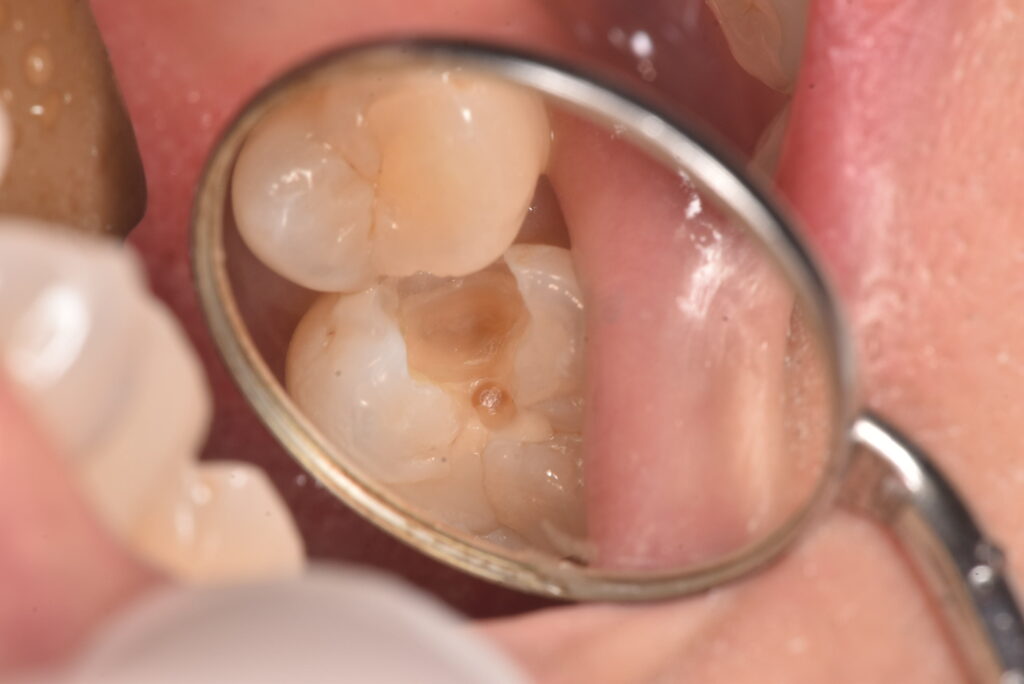

上の写真が処置した部位なります。写真からは、間に黒い部分があるのが見えると思いますが、レントゲン上ではどうでしょうか?

問題の部位は、ここになります。はっきりしたものは映っていません。では、その部分の実際はどうだったのかというと・・・

古いつめものの下の部分も含め、かなりの範囲に広がっていました。それよりも問題なのは、一番最後の写真に写っている削った部分の茶色い部分は、ほぼ神経の真横、ということです。そこまでの大きさなのかは、処置前には全く分かりませんでした。

この状態からは、歯の神経もとることになりえる、ということがお分かりかと思います。一番考えていただきたいこととして、最初の処置前写真から、最後の状態になることを想像できたでしょうか?ということです。

「痛みがなかったのに、歯医者でむし歯があると言われて、治療したら神経をとることになった。おかしい!」に対する回答の一つが上のケースになります。処置前は痛み等の症状はありませんでした。